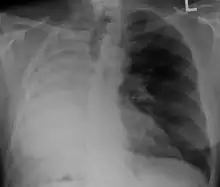

X-ray of a person who has had their right lung removed. Note how fluid has replaced the lung

After a pneumonectomy is performed, changes in the thoracic cavity occur to compensate for the altered anatomy. The remaining lung hyperinflates as well as shifting over along with the heart towards the now empty space. This space is full of air initially after surgery, but then it is absorbed, and fluid eventually takes its place.[9] The fluid which fills the residual space in the chest cavity slowly gelatinizes into a proteinaceous material, and the chest scaffold collapses slightly.